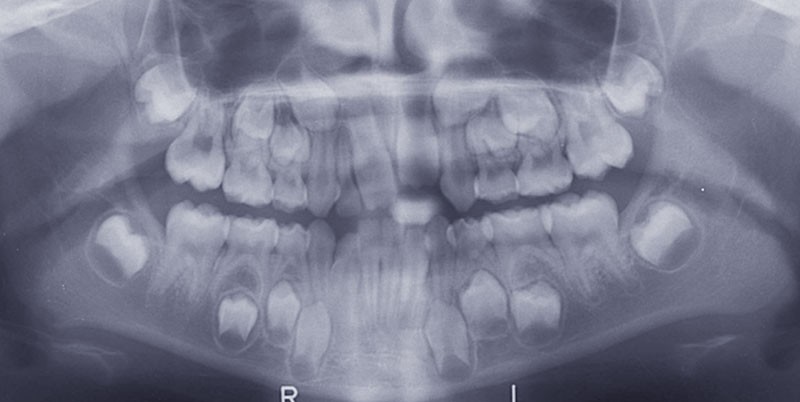

La téléradiographie de début de traitement à 11 ans et demi confirme une évolution en classe I squelettique hypodivergente (fig. 3).